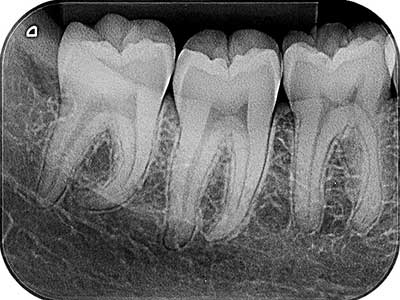

En Odontología Bioestética de Tampico, expertos ondontologos realizamos tu radiografía dental con la tecnología más moderna para poder diagnosticar y dar el mejor tratamiento a cualquier problema o lesión que pudiera arrojar el estudio, no visibles en un examen dental regular.

Certeza:

Para un mejor diagnóstico

Mejor Valoración:

Al permitir observar el nivel del hueso